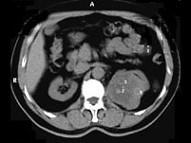

问题 男,65岁,左侧腰背部胀痛伴无痛性全程血尿3个月余,CT平扫及增强检查如图所示,下列说法正确的是 ( )

选项 A、考虑为左侧肾癌 B、考虑为左侧肾错构瘤 C、增强扫描肾皮质期可见肿块明显强化,其内亦有无强化区 D、增强扫描肾实质期可见肿块强化迅速下降,但密度比平扫时仍要高 E、平扫时见左肾上极有一软组织肿块影,其边界较清楚

答案 ACDE